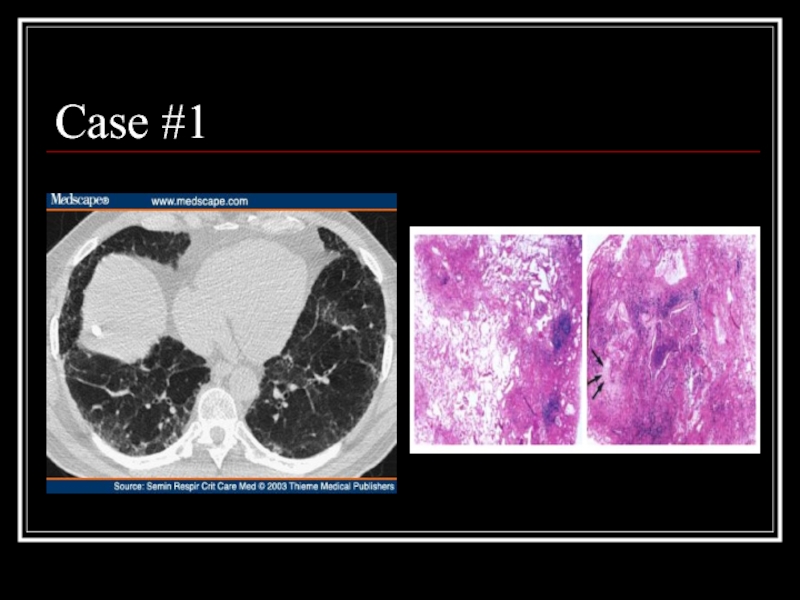

Слайд 19Case #1

Слайд 20Answer: IPF

CT scan: heterogeneous pattern with subpleural disease concentrated posteriorly, traction

bronchiectasis/honeycombing, no nodules, little ground glass

Path: heterogeneous paraseptal collagen deposition and fibroblast foci